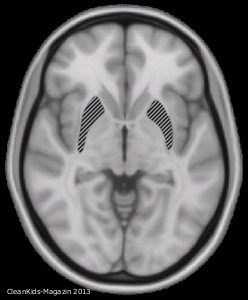

Schädel-Hirn-Trauma (auch SHT)

Die frühzeitig einsetzende aggressive Therapie vermindert Sekundärschäden und ist ausschlaggebend für den Erfolg. Jeder Patient mit SHT sollte 48 Stunden im Krankenhaus überwacht werden (auch wenn lediglich ein SHT 1. Grades, also eine Gehirnerschütterung, vermutet wird).

Die Rückbildung der Symptome bei einer Gehirnerschütterung kann 10 bis 25 Tage dauern, in minderschweren Fällen 3 bis 7 Tage. Sie wird unterstützt durch Ruhe, Vermeiden von Fernsehen, Lärm und Stress.